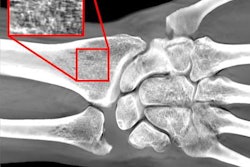

Screening mammography image of same patient taken six months prior. Right mediolateral oblique tomosynthesis image was interpreted as benign, with the circle highlighting postsurgical changes. The cancer diagnosed after MRI screening was confirmed to be an interval cancer.The findings led the authors to question the clinical relevance of DBT for women with a personal history of breast cancer. Although significant, the absolute reduction in the abnormal image interpretation rate was fairly small at 0.4%. Still, the higher specificity could be a benefit for women with prior cancer by reducing the number of women recommended for biopsy.